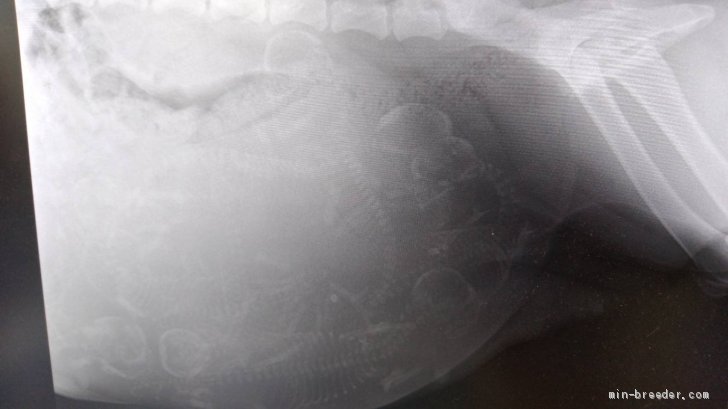

ゴールデンレトリバー妊娠エコー検査❇️ゴールデンレトリバーのニコルちゃんいよいよ出産間近❇️ お腹にいる赤ちゃんの頭数確認の為...